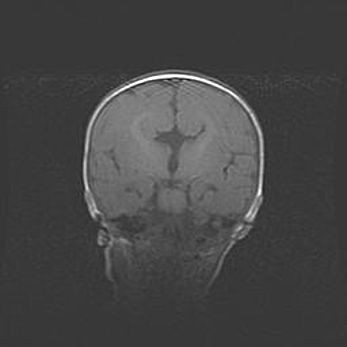

Наружная гидроцефалия с возможной атрофией височных областей.

Возраст: 28 дней

Вес: 3670 г

Пол: мужской

Окружность головы: 38 см

Срок гестации: 40 недель

Гидроцефалия головного мозга у новорожденных – это заболевание, которое характеризуется скоплением избыточного количества спинномозговой жидкости в желудочковой системе головного мозга в результате затруднения её перемещения от места выработки к месту поглощения в кровеносную систему или вследствие нарушения абсорбции. При открытой наружной форме гидроцефалии у новорожденных расширяются и переполняются субарахноидные пространства.

При нормотензивных  формах,  которые,  как  правило,  являются  следствием  перенесенных ишемических  повреждений  паренхимы  мозга,  возможно  сочетание микроцефалии  с нормотензивной гидроцефалией. В основе данных изменений лежит атрофия больших полушарий с преимущественной  локализацией  в  лобно-височных  областях.